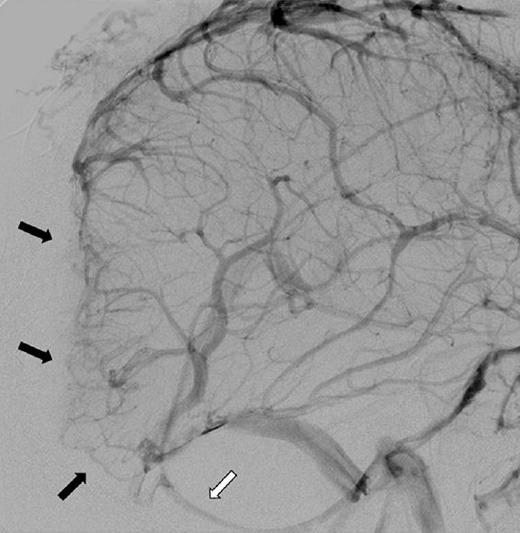

A 48-year-old male presented after 3 days of worsening headaches and blurry vision. Preoperative imaging demonstrated an 11 × 5-cm extra-axial mass that avidly enhanced with gadolinium in the region of the torcula. Angiography demonstrated occlusion of the involved portions of the superior sagittal sinus, torcula, and proximal left transverse sinus. Cortical drainage occurred via the veins of Labbι and deep drainage via an occipital sinus. Using image-guided stereotaxy, a wide-excision scalp resection and craniectomy with sinus exploration was planned for complete tumor removal. Parasitized cortical veins were preserved. Occluded portions of the superior sagittal sinus and left transverse sinus were resected along with the invaded parts of the falx and tentorium. The walls of the straight sinus, torcula, and right transverse sinus were repaired primarily to facilitate deep drainage. A latissimus dorsi free flap was used to reconstruct the scalp defect. Routine follow-up magnetic resonance imaging (MRI) at 18 months demonstrated no evidence of recurrence or regrowth.

一名48岁男性在头痛和视力模糊加重3天后就诊。术前影像学检查显示一个11×5厘米的轴外肿块,在窦汇区域钆增强明显。血管造影显示上矢状窦、窦汇和左侧横窦近端受累部分闭塞。皮质引流通过Labbe静脉进行,深部引流通过枕窦进行。采用影像引导立体定向技术,计划进行广泛的头皮切除和颅骨切除术并探查窦,以完整切除肿瘤。保留寄生的皮质静脉。切除上矢状窦和左侧横窦的闭塞部分以及镰和小脑幕的受累部分。直接修复直窦、窦汇和右侧横窦的壁以促进深部引流。使用背阔肌游离皮瓣修复头皮缺损。18个月的常规随访磁共振成像(MRI)显示无复发或再生长迹象。